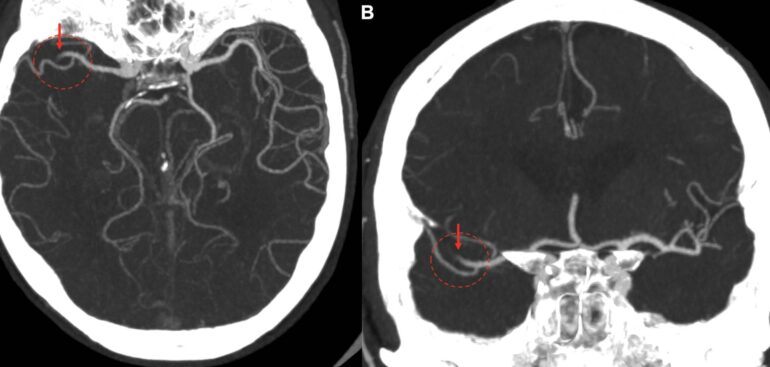

«Questa tipologia di pazienti è stata oggetto del nostro studio –  spiega l’esperto – e in particolare quei pazienti in cui l’occlusione viene documentata in un tratto più periferico dell’arteria cerebrale media (quello che viene definito tratto M2). Sebbene questo segmento dell’arteria cerebrale media sia trattabile attraverso una procedura endovascolare (la trombectomia meccanica), le attuali linee guida di trattamento dell’ictus in fase acuta sconsigliano questa procedura nei pazienti con un grado lieve di compromissione clinica. Tuttavia – precisa – la principale perplessità nella gestione di questi pazienti nasce dal fatto che una percentuale di questi (che nella nostra casistica è del 40% circa), pur avendo al principio sintomi minimi, può andare incontro ad un peggioramento clinico notevole» Dallo studio è emerso ad esempio che la presenza di fibrillazione atriale è un elemento predittivo di deterioramento clinico.